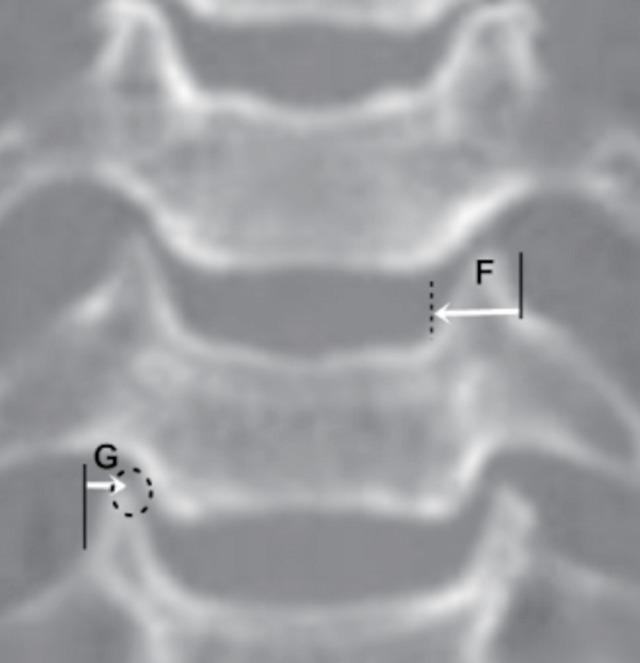

The purpose of this study was to provide anatomical data on the dimensions and location of the subaxial transverse foramen (TF) in relation to surgical landmarks routinely used during anterior cervical procedures.

METHODS

A total of 116 patients who underwent preoperative computed tomography (CT) evaluations for degenerative cervical disease were enrolled. Axial and coronal CT images of the cervical vertebrae from C3 to C6 were analyzed to measure interforaminal distance, the TF distance from the anterior and posterior vertebral body margin, TF dimensions, and the TF medial margin from the tip and medial margin of the uncus. Comparative and correlative analyses were also performed according to age, body mass index (BMI), and sex.

All measurement values in male patients were larger than those in their female counterparts. The interforaminal distance gradually increased from C3 to C6. The distance of the TF medial margin from the tip of the uncus was found be above approximately 3 mm in all vertebrae except C6. Correlation analysis revealed that age had a significant negative relationship with the transverse diameter of TF. In contrast, BMI had a significant positive correlation with interforaminal distance. Moreover, the distances of the TF medial margin from the tip and medial margin of the uncus showed strong negative correlations with age.

Useful morphometric data were obtained that may help the operating surgeon to avoid vertebral artery injury. The safe distance from the tip of the uncus to the TF medial margin was found to be approximately 3 mm, and this distance should not be violated during lateral decompression. In addition, this value may decrease with age.

本研究旨在提供关于下颈椎横突孔(TF)的尺寸和位置的解剖学数据,这些数据与颈椎前路手术中常规使用的手术标志相关。

方法

共纳入116例因颈椎退行性疾病接受术前计算机断层扫描(CT)评估的患者。分析C3至C6颈椎的轴向和冠状位CT图像,以测量椎间孔间距、TF与椎体前后缘的距离、TF尺寸以及TF内侧缘与钩突尖端和内侧缘的距离。还根据年龄、体重指数(BMI)和性别进行了比较和相关性分析。

男性患者的所有测量值均大于女性患者。椎间孔间距从C3到C6逐渐增加。除C6外,在所有椎体中,TF内侧缘与钩突尖端的距离均在约3 mm以上。相关性分析显示,年龄与TF的横径呈显著负相关。相反,BMI与椎间孔间距呈显著正相关。此外,TF内侧缘与钩突尖端和内侧缘的距离与年龄呈强烈负相关。

获得了有用的形态学数据,可能有助于手术医生避免椎动脉损伤。发现钩突尖端到TF内侧缘的安全距离约为3 mm,在进行侧方减压时不应侵犯此距离。此外,该值可能随年龄增长而减小。